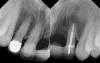

The chief complaint of a 48-year-old woman who presented to her restorative dentist was, “I don’t like the way my implant looks” (Figure 1). This implant had been placed by a previous periodontist and restorative dentist. The patient is now seeking a second opinion. In evaluating this case upon referral to the periodontist, a reddened appearance of the gingival and mucosal tissue encompassing almost the entire facial aspect could be observed. In addition, the radiographs demonstrated a 5-mm diameter implant in place with a deciduous cuspid in the place of No. 11. Deep probing depths were noted around the facial aspect of the implant, and threads could be detected under the tissue.

Figure 1  (Case 1) Initial presentation of restored implant No. 10.

Figure 1